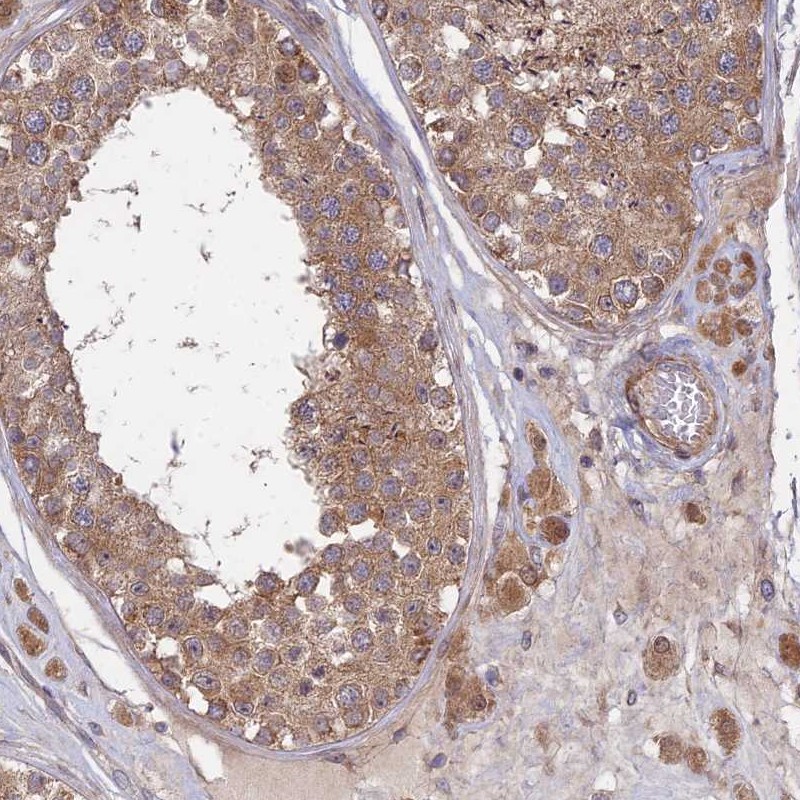

Immunohistochemical staining of human testis shows moderate cytoplasmic positivity in cells in seminiferous ducts and Leydig cells.